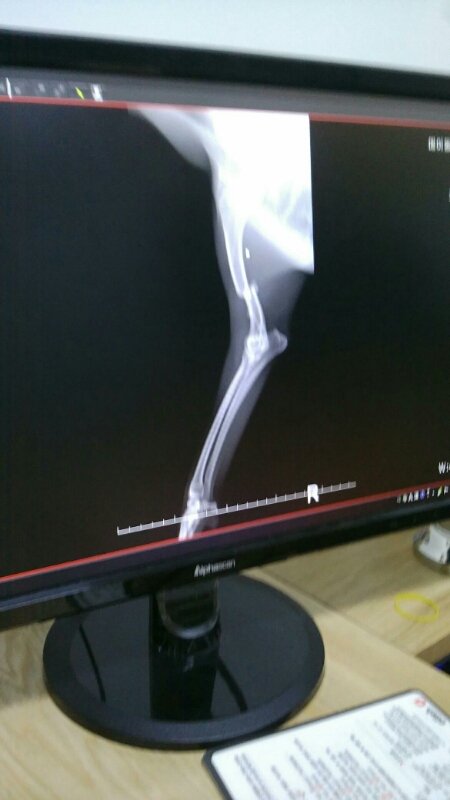

24시병원으로 옮겨 검진결과

앞두다리 골절과 골반 양쪽골절.

심장비대 신장기능이 멈춰 몸에 독소가 가득하답니다.

2~3일 지켜본후 수술여부를 결정한다고 하십니다.